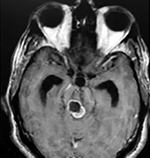

Paciente femenino de 29 años de edad con historial de cefalea crónica que presenta súbitamente disdiadococinesia y dismetría izquierda.

El estudio de RMN presenta una lesión bien circunscrita en hemisferio cerebeloso izquierdo con periferia de predominio hiperintenso en T1 y T2, y centro hipointenso, edema perilesional mínimo, así como una imagen de un vaso venoso alimentador que recorre hacia el ángulo pontocerebeloso izquierdo.

El estudio de control de RMN se observa la brecha quirúrgica y ausencia de lesión (figs. 1, 2 y 3).

Figura 1:

Lesión cerebelosa izquierda ponderaciones en T1 y T2, la flecha señala vaso nutricio hacia el ángulo pontocerebeloso izquierdo, se puede observar el centro de intensidad heterogénea con contenido quístico multiloculado y edema perilesional leve.